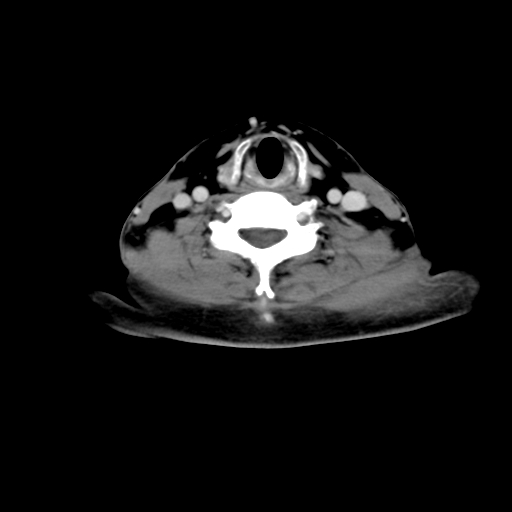

标题: CT24019:男,45岁,发现颈部肿物5个月。 [打印本页]

男,45岁,发现颈部肿物5个月,彩超示:双侧颈部及下颌部软组织增厚。

考虑双侧颈项部良性对称性脂肪增多症。